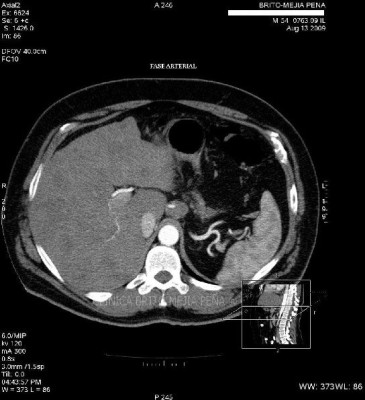

Metástasis hígado fase arterial